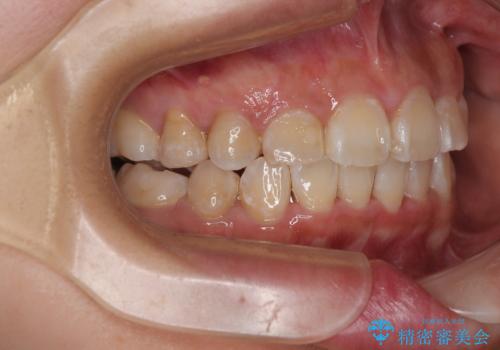

- 上下前歯のデコボコを気にして来院された患者様です。

上顎は両側の犬歯が骨内に埋伏しており、乳歯が残存している状態でした。

歯肉内に埋もれている場合には牽引することも可能ですが、両歯ともに骨内に完全に埋もれていたため、牽引することは不可能と判断しました。

口元の突出感があるわけではなく、叢生の程度もシビアではありませんでしたが、顎骨が小さく、左右ともに最後臼歯が歯肉に埋もれているため、下顎は左右第二小臼歯を抜歯することとしました。

上顎は左右ともに残存している乳歯を抜歯し、上下歯列を整えることとしました。